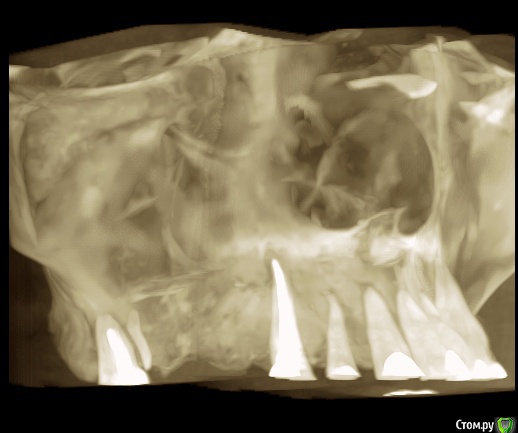

olersh Опубликовано 4 ноября, 2015 Поделиться Опубликовано 4 ноября, 2015 Здравствуйте, уважаемые доктора!20 октября 2015 г. начала лечить заболевший 17 зуб с диагнозом периодонтит. Из коренных он остался единственный - хожу с "мостом". Зуб решили сохранить и сразу начали лечение (снимки сделали после лечения, их приложить не могу, ибо не выдали). Ввели лекарство на две недели - следующий прием назначили на 3 ноября. Назначили найз через 12 часов, пока есть боль. Зуб болел достаточно сильно после лечения, но врач сказала терпеть или удалять. Решила терпеть. С 23 по 27 поднялась была температура в среднем 37,5 °С.29 октября вдруг через носоглотку стал выделяться гной с жутким запахом и первые несколько часов еще и ужасной горечью. Зуб сразу стал меньше болеть. Позвонила врачу, спросила - не может ли произойти прободение из полости зуба в пазуху. Врач сказала, что у меня гранулема, и, возможно, она разрушается под воздействием лекарства, успокоила, что ничего страшного, день приема не перенесла, про лекарства тоже ничего нового не сказала (продолжаю пить найз).31 октября, в субботу снова позвонила врачу (страшно мне из-за гноя). Попросила выписать хотя бы антибиотик. Выписали амоксиклав 1000. Предположили, что у меня обычный гайморит (раньше никогда не болела этой заразой), предложили обратиться к лору, чтобы выяснить, можно ли лечить зуб или надо его удалять.2 ноября сходила в челюстно-лицевую хирургию. Они подтвердили, что надо к лору, но сказали, что лучше сделать снимок КТ, на котором должна быть видна перфорация, если она есть. 3 ноября сделала КТ, с ним пришла на прием к стоматологу. В итоге КТ толком не посмотрели, но снова отправили к лору - пойду завтра.Уважаемые стоматологи, посмотрите, пожалуйста, снимки! Если необходимо, могу выложить в других ракурсах или даже сам файл прислать, если у вас есть такая программа. Ссылка на комментарий

red_butler Опубликовано 4 ноября, 2015 Поделиться Опубликовано 4 ноября, 2015 Спасибо! Если можно, приведите, пожалуйста, аргументы, хотя бы вкратце?перелом корня, это не лечится 2 Ссылка на комментарий